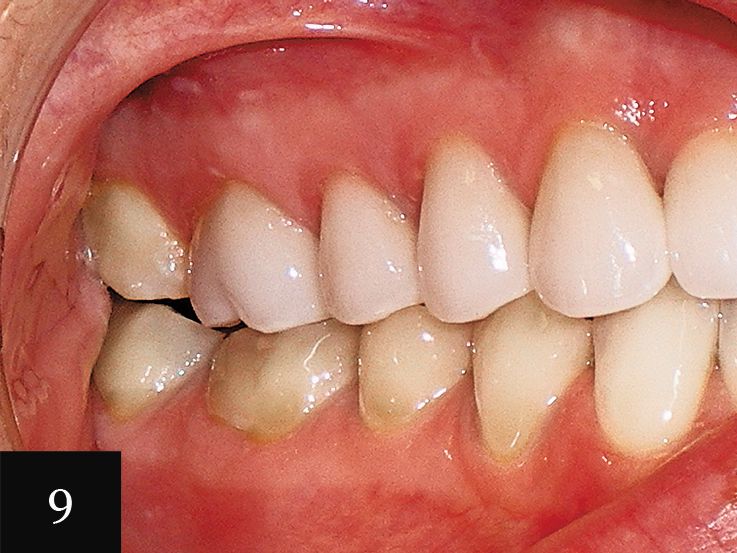

Case No. 3

This treatment was performed on a male patient in his early 40s (Fig. 9). The patient had an omega-shaped upper arch, as seen in Fig. 10.

An impression was taken that successfully captured the complex crowding and narrow omega arch (Fig. 11), and the patient was treated with 28 aligners over 14 months. This case also illustrates use of the clear aligners as whitening trays, with the final result showing a smile that is not only straight, but also much brighter (Figs. 12-14).